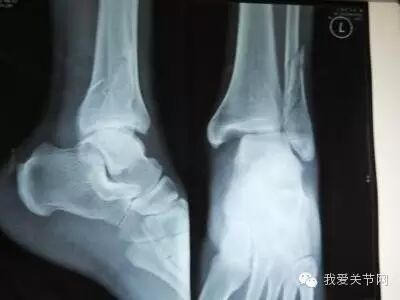

赛后确认邹正为腓骨骨折,脚踝脱位,近期将在日本接受手术。由于无法获知邹正准确的伤情,但是我们从受伤的部位可以对恢复时间做个大致的判断 踝关节内骨折,因累及软骨受损,软骨受损会引起创伤性关节炎,引起踝部慢性疼痛,软骨受损休整后需要8-12月的修复过程。

图文无关